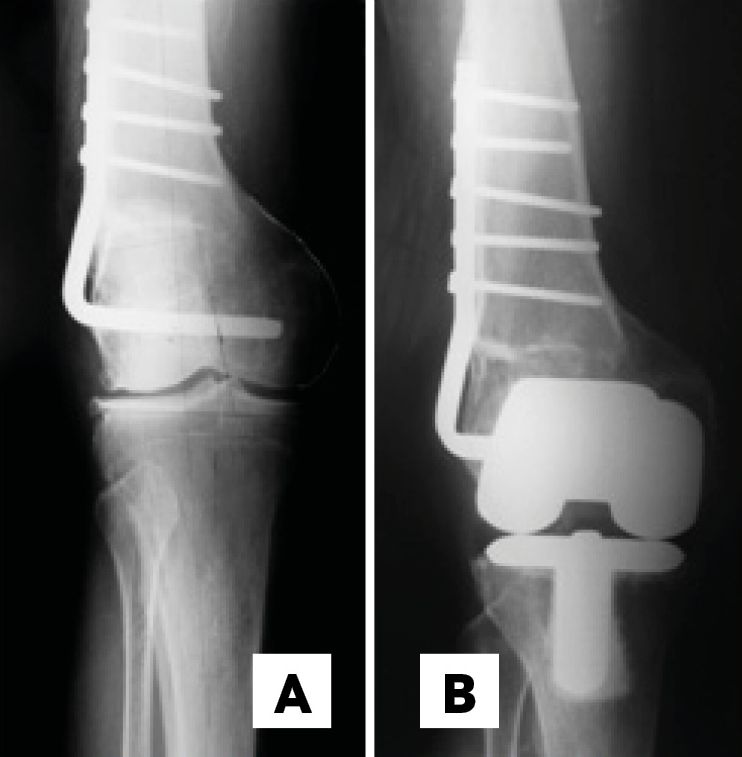

B. Supracondylar Femoral osteotomy in 10 knees, 7 varus (Figure 1) and 2 valgus

There were 16 varus knees (average intra-articular deformity 9.2°) and 13 valgus knees (average intra-articular deformity 16.6°). The extra-articular deformity was situated in the distal third of the femur in 12 (Figure 1), in the middle third of the femur in 4 patients (Figures 2 & 3), in the proximal third of the tibia in 9 and in the middle third of the tibia in 4 . Regarding the type of deformity, all patients had a coronal deformity, 13 in varus (average 16.3°), 15 in valgus (average 14.4°) and 1 with a medial displacement of the distal femoral epiphysis of 3 cm. (Figure 1). In 8 patients, the deformity was biplanar with alterations in the sagittal plane, 4 in flexion and 4 in extension, with an average of 19.7° and 8° respectively. No patients showed a significant rotational deformity.

The distal femoral bone cut can be planned using as reference the femoral mechanical axis (cut in 90°) or preferably the axis of the femur proximal to the deformity. The correction of the extra-articular deformity can be made through intra-articular cuts when the femoral distal cut line respects the MCL insertion, since on the lateral side, a lateral epicondylar osteotomy can be performed similar as when dealing with severe valgus deformities. (Figure 5 A & B). [2], Mullaji Arun, Shetty GM Computer-Assisted Total Knee Arthroplasty for arthritis with extra-articular deformity. J. Arthroplasty. 2009;24(8):1164.[3], Panayiotis JP, Karachaloios T, Themistocleous GS Total knee arthroplasty in patients with pre-existing fracture deformity. Orthopedics. 2007;30(5):373.[4], Wolff AM, Hungerford DS, Pepe CL The effect of extraarticular varus and valgus deformity on total knee arthroplasty. Clin Orthop. 1991;271:35-51.[6],Wang JW, Wang CJ Total knee arthroplasty for arthritis of the knee with extra-articular deformity. JBJS Am. 2002;84(10):1769-1774.[8], Mann JW, Insall JN, Scuderi GR Total knee arthroplasty in patients with associated extra-articular angular deformity. Orthop Trans. 1997;21:59.[15] Rand JA, Franco MG Revision considerations for fractures about the knee. In: Goldberg VM (Ed.), Controversies of total knee arthroplasty. Raven Press Ltd, New York, USA, pp. 1991;235-247.